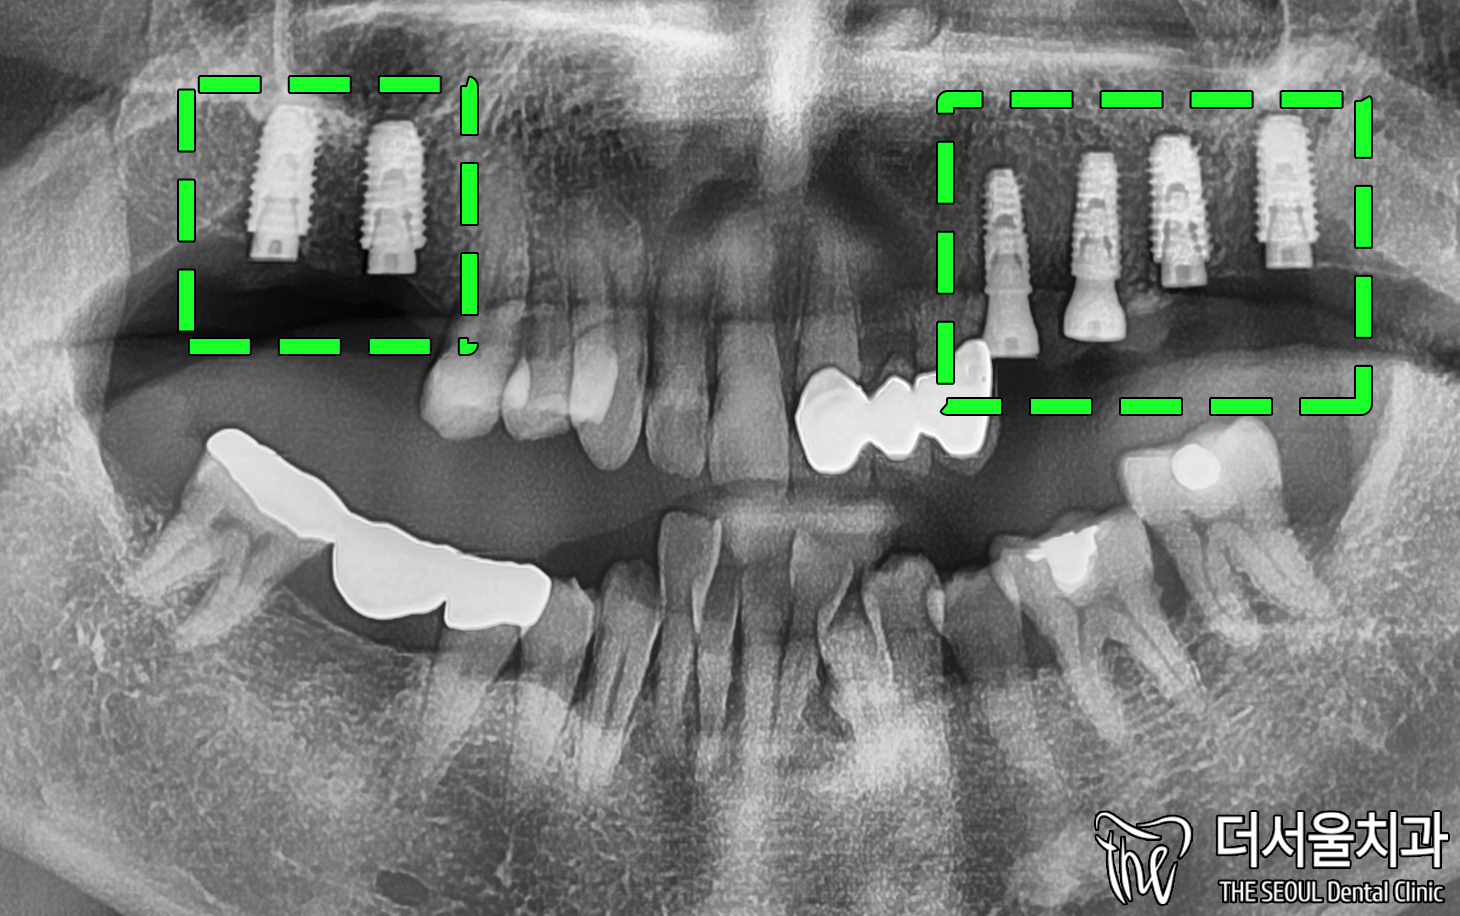

1. 체크

성남 치과는 정면을 먼저 눈으로 확인했습니다.

상태가 많이 좋지 않았습니다.

뼈 소실 또한 큰 것으로 보여집니다.

뼈이식을 추천 드리게 될 것이라 예측되는데요.

교합면을 보면 뼈가 고르지 않고

조금 편평하게 변한 것을 볼 수 있죠.

임플란트 수술을 진행함에 있어

살짝 난항이 있을 것이라 예측되었습니다.

좀 더 정확한 데이터가 필요했기에

디지털 프로그램을 이용하여 체크했습니다.